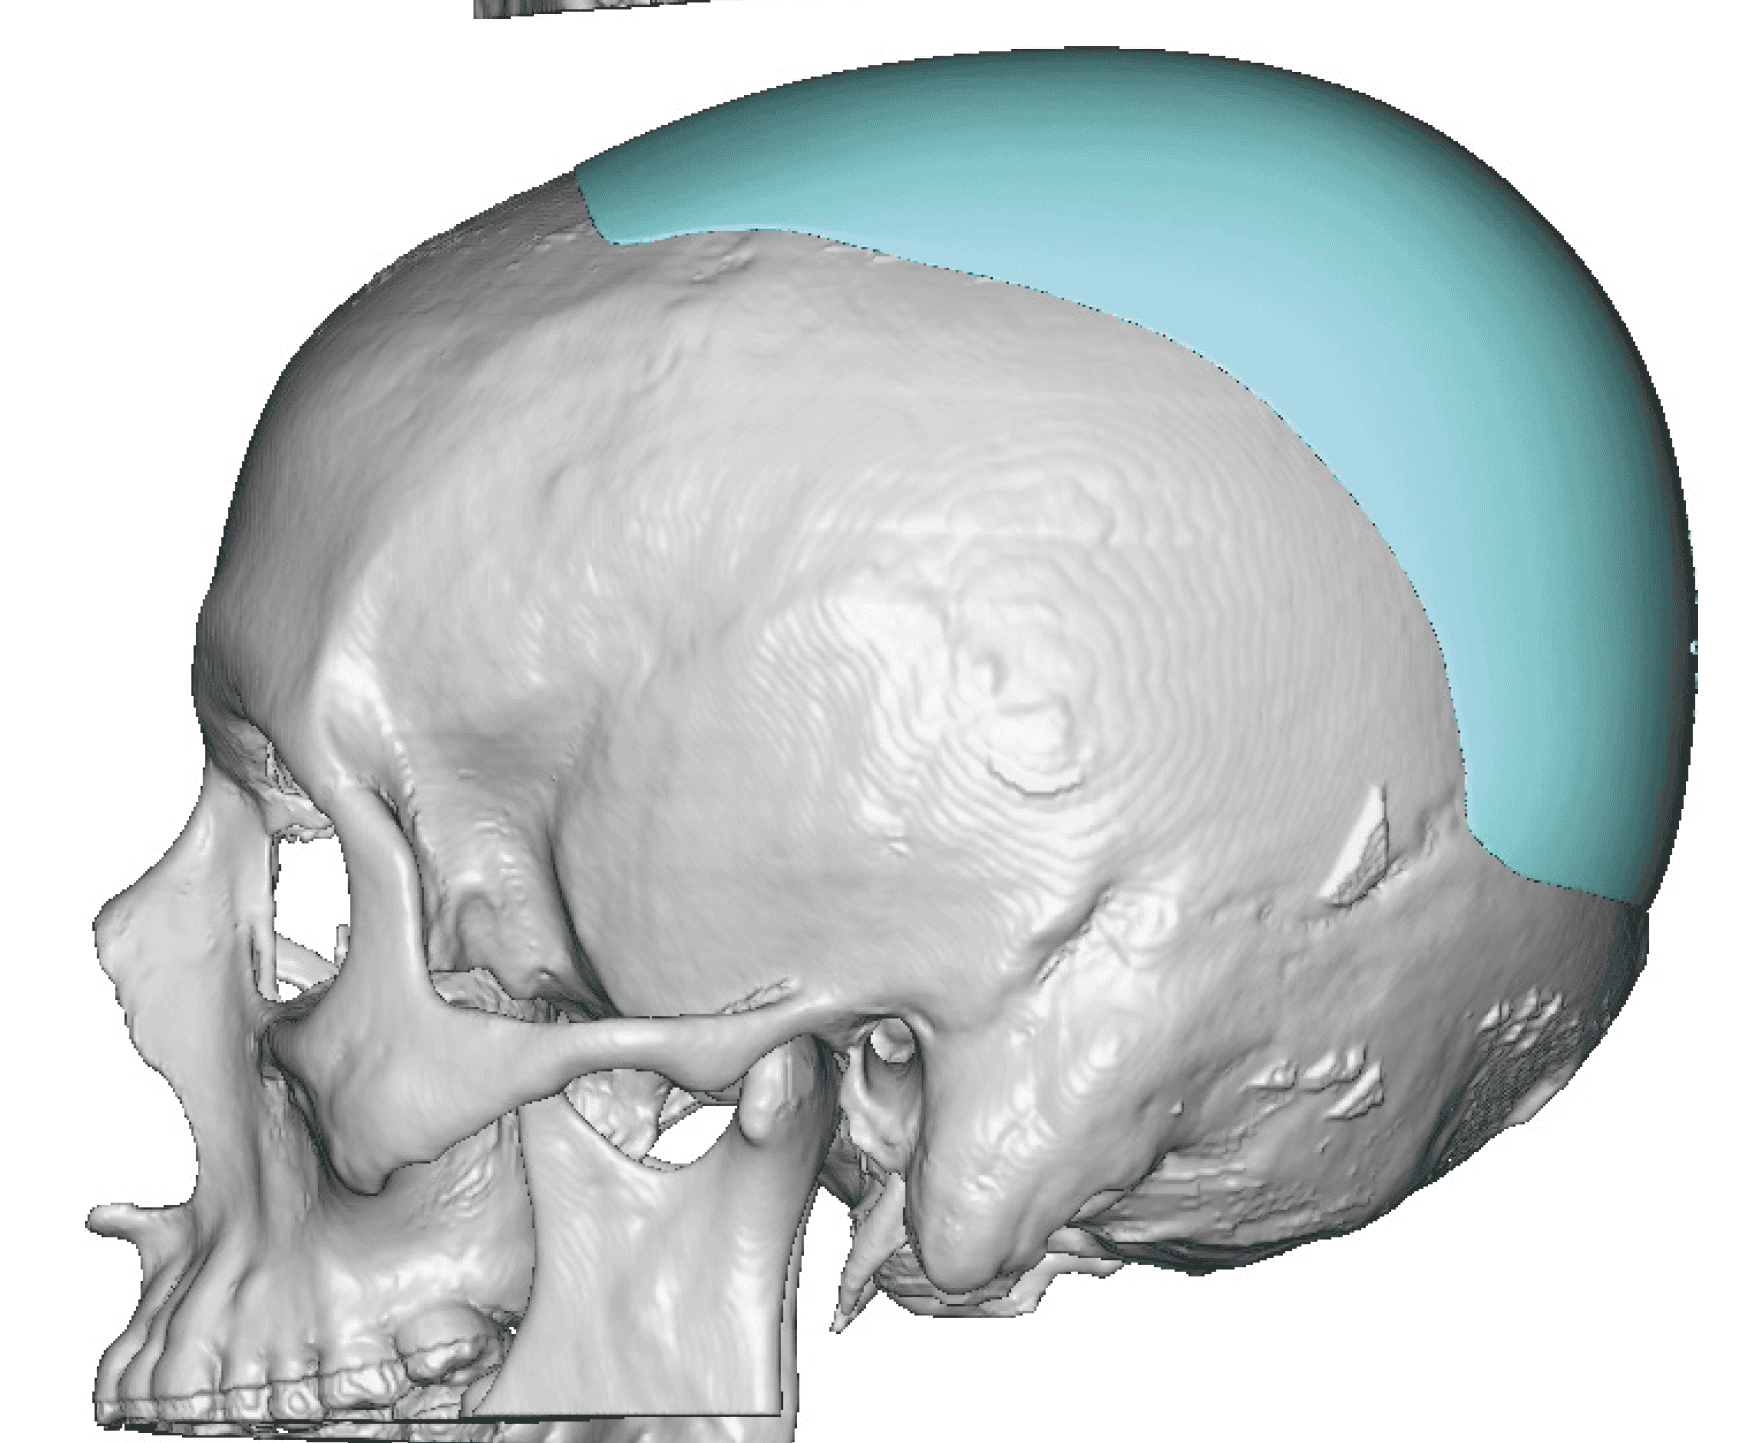

Patient 49

Desire for further skull augmentation after a primary skull implant.

Five years after an initial custom skull implant placement a new custom skull implant that increased the volume by 35% was placed.

Desire for further skull augmentation after a primary skull implant.

Five years after an initial custom skull implant placement a new custom skull implant that increased the volume by 35% was placed.